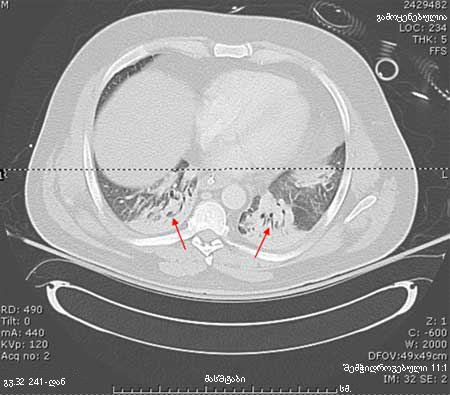

პაციენტის კომპიუტერული ტომოგრაფია, რომელსაც აქვს HAP, გვიჩვენებს ორმხრივ ბაზილარულ დაჩრდილვას.